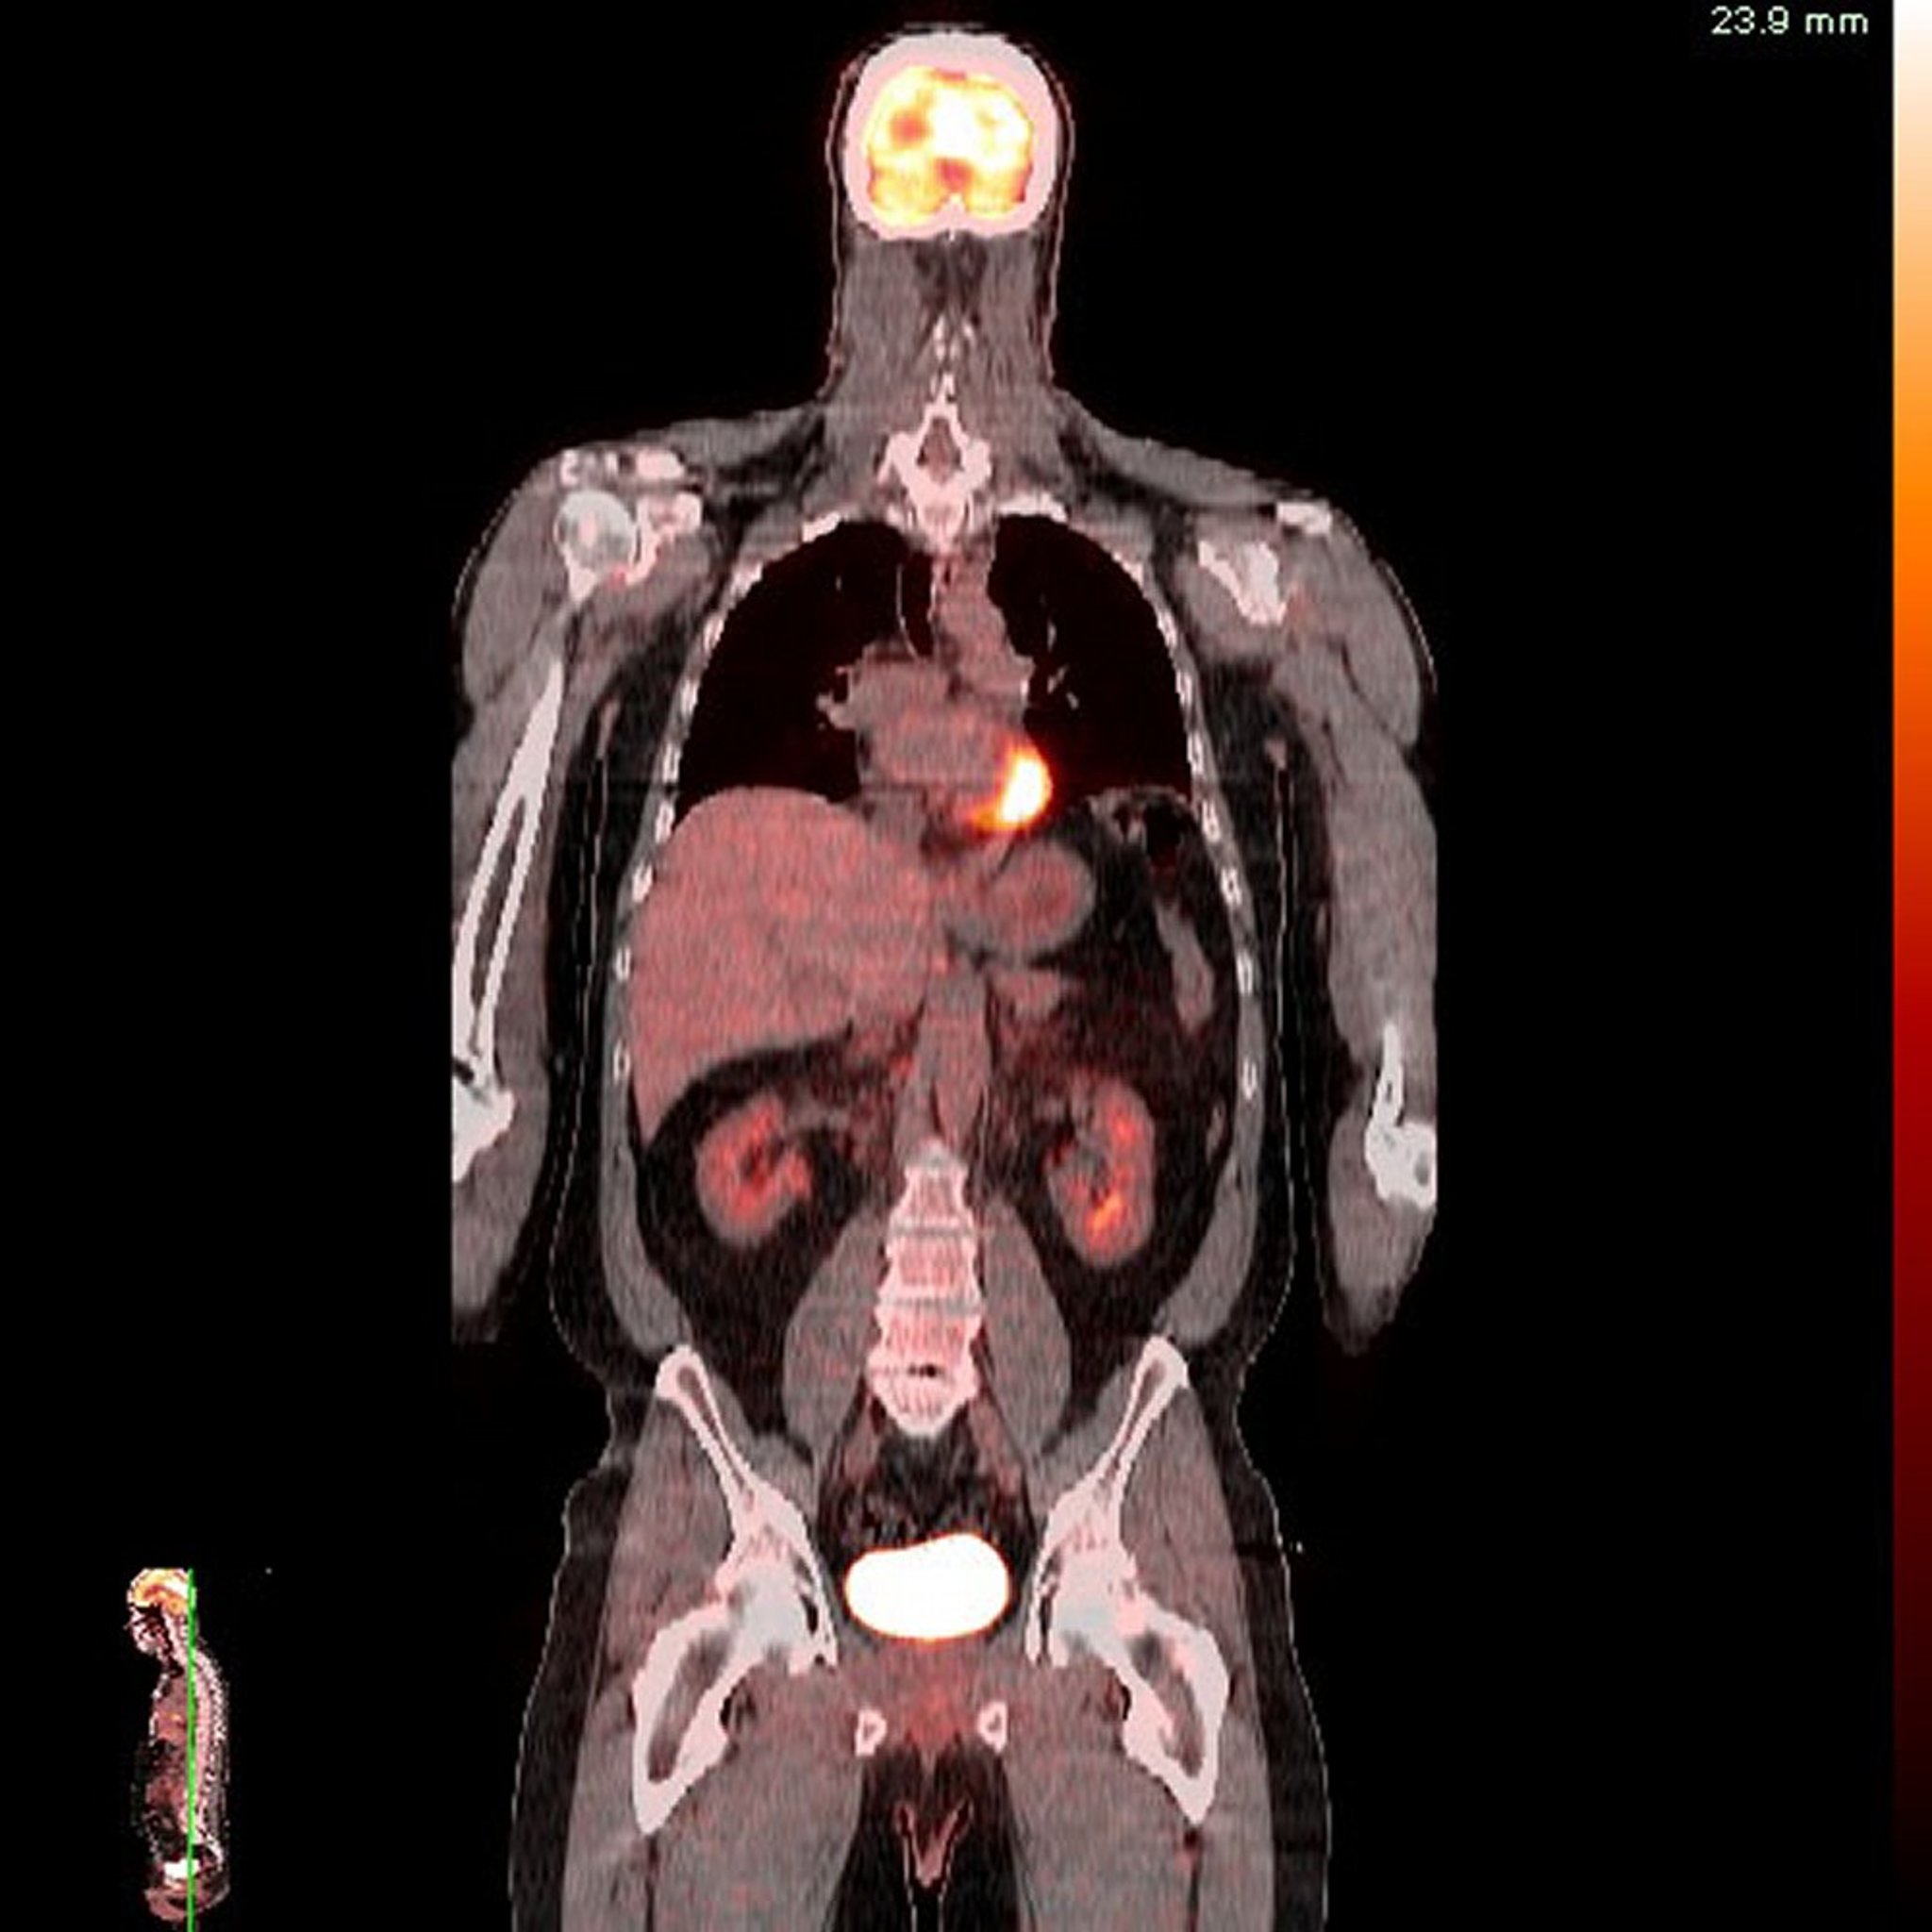

Gambar menunjukkan tingkat aktivitas yang berbeda dalam intensitas warna yang berbeda. Dengan demikian, PET dapat memberikan informasi tentang fungsi jaringan dan dapat mengidentifikasi jaringan yang tidak normal, yang mungkin lebih atau kurang aktif dibandingkan jaringan normal. Akan tetapi, PET tidak menunjukkan detail anatomi dan struktural jaringan dan organ serta tomografi terkomputasi (CT) atau pencitraan resonansi magnetik (MRI).

PET biasanya dikombinasikan dengan tomografi terkomputasi (CT). PET-CT memberikan gambar 2 dimensi terperinci yang menunjukkan anatomi (melalui CT) dan fungsi (melalui PET). Dua gambar (gambar CT dan PET) dapat dilihat secara terpisah, atau salah satunya dapat dihamparkan di atas gambar lainnya. Dengan demikian, teknik ini memberikan informasi yang berguna tentang anatomi dan fungsi serta dapat membantu dokter mengidentifikasi ketidaknormalan yang memengaruhi anatomi dan/atau fungsi.

Teknik ini sangat berguna untuk kanker pada bagian tubuh yang memiliki banyak jaringan berbeda yang berdekatan, seperti leher dan panggul. Zat ini membantu menemukan kanker dengan tepat dan dapat mendeteksi kekambuhan dini.